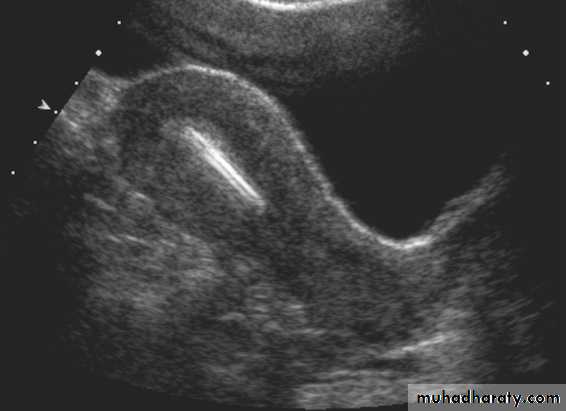

Submucosal fibroid. (a) Transvaginal US image reveals a uterine mass (arrows) with posterior acoustic shadowing.• Pathology of Endometrium